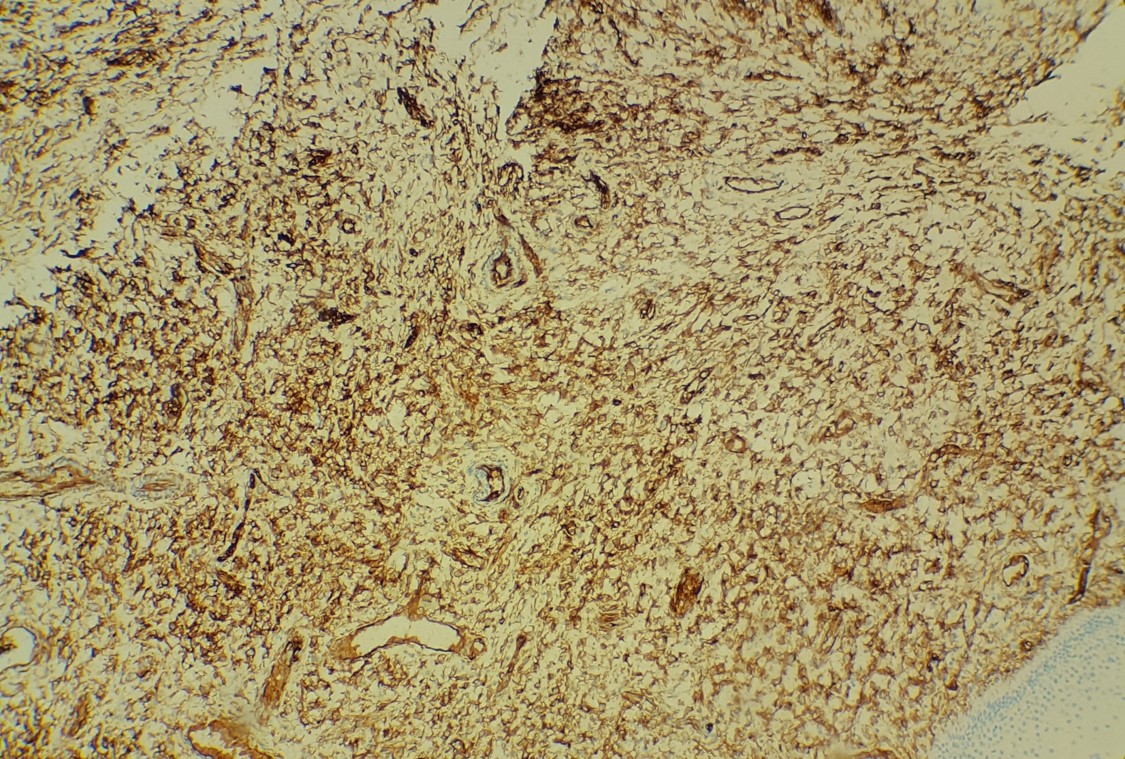

The findings in this case show a submucosal, nodular mass of bland spindle to oval cells and scattered mast cells in a background of thick collagen material. No atypia or mitotic figures are identified. The overlying mucosa is unremarkable. The immunoprofile of this lesion is CD34 and desmin positive, S-100 negative.

Superficial myofibroblastomas occur in adults and typically present as a superficial mass in the vagina, vulva, or cervix and average 2 to 3 cm in size. Microscopically, a moderately cellular proliferation of bland spindle cells are noted within collagenous stroma. Multiple patterns of growth can be present, including lacelike, fascicular, storiform, myxoid, and hyalinized, but a patternless pattern is most common. Thin-walled blood vessels can be seen concentrated in the center of the lesion. The immunoprofile shows positivity for ER, PR, desmin, vimentin staining and variable positivity for CD34. Keratins and S-100 are negative. Treatment is complete local excision as they have been reported to recur if incompletely excised.